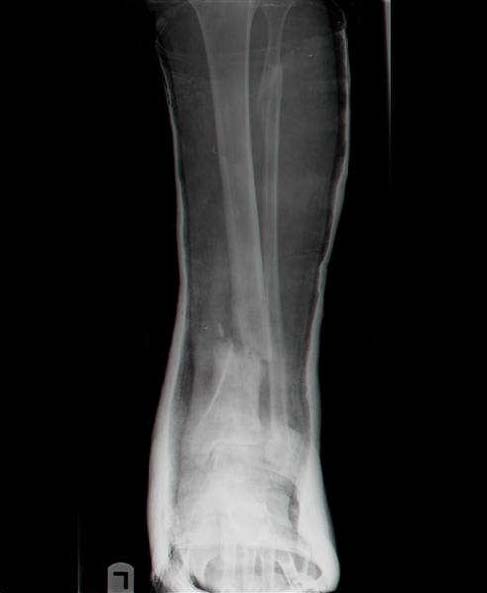

Sorry, I wiil tray now pictures of my case.